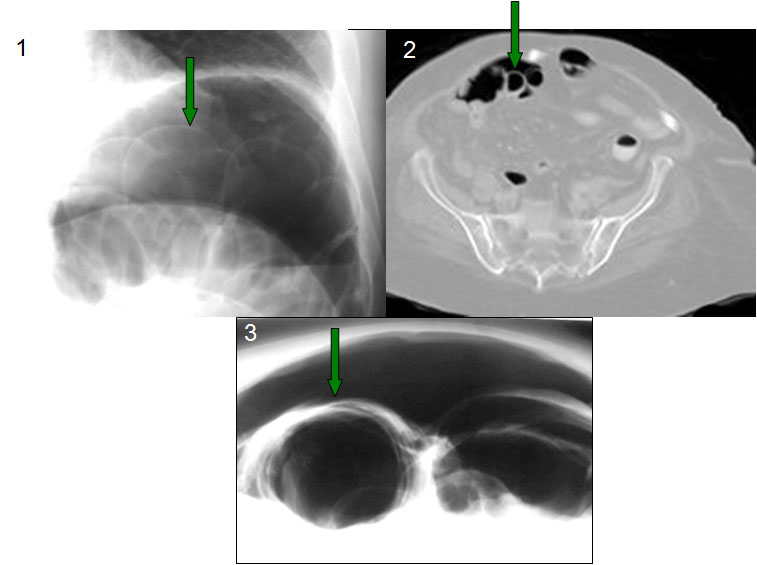

SIGNO DE LA DOBLE PARED O SIGNO DE RIGLER

En la radiografía simple de abdomen, la presencia de aire a ambos lados de la pared gástrica o intestinal, indica la existencia de neumoperitoneo.

La detección de este signo es importante en pacientes que, por su estado, no pueden adoptar la posición erecta o el decúbito lateral. Se ha descrito una imagen similar cuando se yuxtaponen dos asas intestinales distendidas, en pacientes sin neumoperitoneo.

Este signo puede verse también en la radiografía de tórax (1), en la TC (2), y en la placa de abdomen en decúbito supino con rayo horizontal (3) aunque, en general, se requieren cantidades mayores de neumoperitoneo para su demostración.